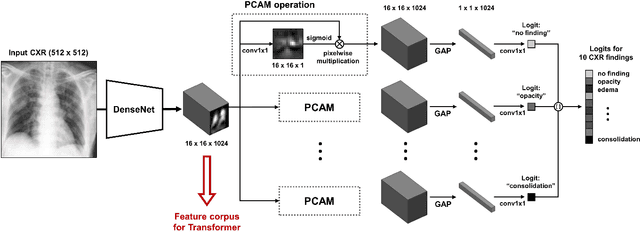

Abstract:Developing a robust algorithm to diagnose and quantify the severity of COVID-19 using Chest X-ray (CXR) requires a large number of well-curated COVID-19 datasets, which is difficult to collect under the global COVID-19 pandemic. On the other hand, CXR data with other findings are abundant. This situation is ideally suited for the Vision Transformer (ViT) architecture, where a lot of unlabeled data can be used through structural modeling by the self-attention mechanism. However, the use of existing ViT is not optimal, since feature embedding through direct patch flattening or ResNet backbone in the standard ViT is not intended for CXR. To address this problem, here we propose a novel Vision Transformer that utilizes low-level CXR feature corpus obtained from a backbone network that extracts common CXR findings. Specifically, the backbone network is first trained with large public datasets to detect common abnormal findings such as consolidation, opacity, edema, etc. Then, the embedded features from the backbone network are used as corpora for a Transformer model for the diagnosis and the severity quantification of COVID-19. We evaluate our model on various external test datasets from totally different institutions to evaluate the generalization capability. The experimental results confirm that our model can achieve the state-of-the-art performance in both diagnosis and severity quantification tasks with superior generalization capability, which are sine qua non of widespread deployment.

Abstract:Under the global COVID-19 crisis, developing robust diagnosis algorithm for COVID-19 using CXR is hampered by the lack of the well-curated COVID-19 data set, although CXR data with other disease are abundant. This situation is suitable for vision transformer architecture that can exploit the abundant unlabeled data using pre-training. However, the direct use of existing vision transformer that uses the corpus generated by the ResNet is not optimal for correct feature embedding. To mitigate this problem, we propose a novel vision Transformer by using the low-level CXR feature corpus that are obtained to extract the abnormal CXR features. Specifically, the backbone network is trained using large public datasets to obtain the abnormal features in routine diagnosis such as consolidation, glass-grass opacity (GGO), etc. Then, the embedded features from the backbone network are used as corpus for vision transformer training. We examine our model on various external test datasets acquired from totally different institutions to assess the generalization ability. Our experiments demonstrate that our method achieved the state-of-art performance and has better generalization capability, which are crucial for a widespread deployment.